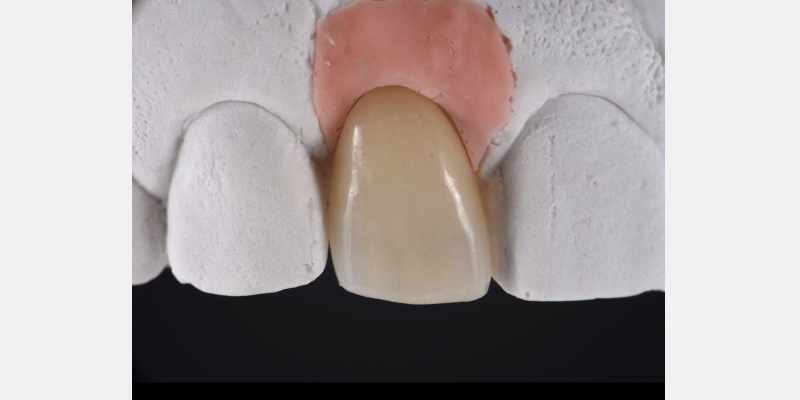

Here is a simple, step-by-step technique for fabricating a silicone jig to avoid excess cement in a cement-retained implant-supported restoration. It can be applied to a single crown or to an implant-supported cement-retained bridge.